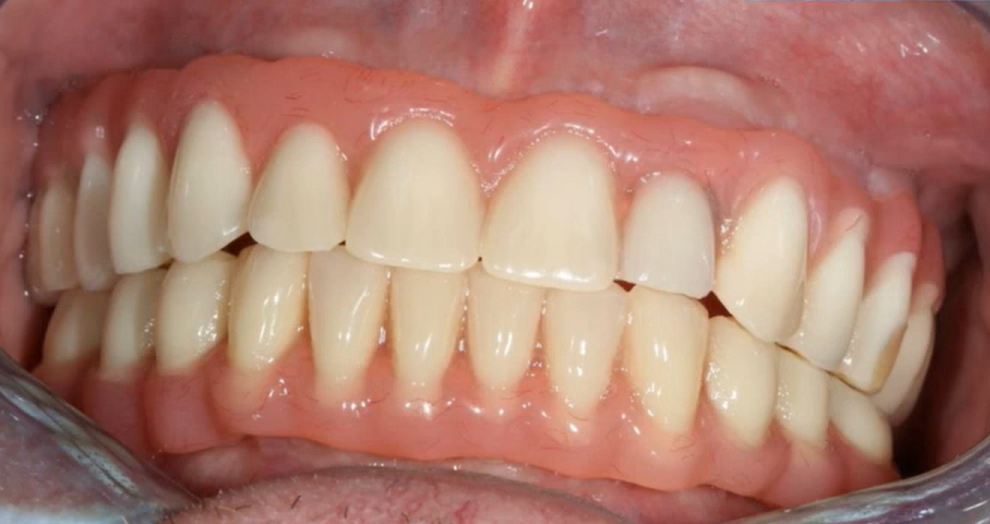

If there are remnants of teeth or old prostheses, the task is easier, but the volume and complexity of the work remain high. In the images below are several examples of restorations.

A PFM mandible prosthesis supported by 4 implants – optimal height of the Full-Arch prosthesis. YouTube/ Dr. Sergey Rozhnov /sergiodontologist

The images above show a classic PFM prosthesis supported by four implants. The restoration has been successfully in place for over five years. This is an example of optimally executed work, considering the height and overall configuration of the prosthesis. Such a prosthesis will not act as a massive lever and transfer excessive load to the implants. However, it is not ideal either. Given the volume of the metal frame, veneering material will be thin. This results in frequent chips, cracks, and frequent requests for correction.The following images show a much more complex situation. This is a temporary denture for immediate loading, made directly without the need for a dental laboratory. Note the height of this denture.